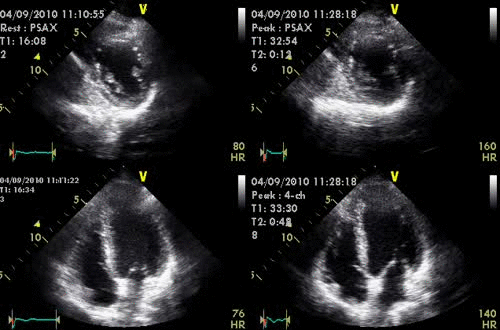

Ecocardiografía de Esfuerzo

La ecocardiografía de esfuerzo emplea ondas de sonido (ultrasonido) para producir una imagen del corazón y ver cómo funciona. La ecocardiografía de esfuerzo permite examinar el movimiento de las paredes de las cavidades de bombeo del corazón, antes y después del ejercicio. La prueba permite determinar si ciertas regiones del músculo cardíaco no reciben suficiente sangre rica en oxígeno.